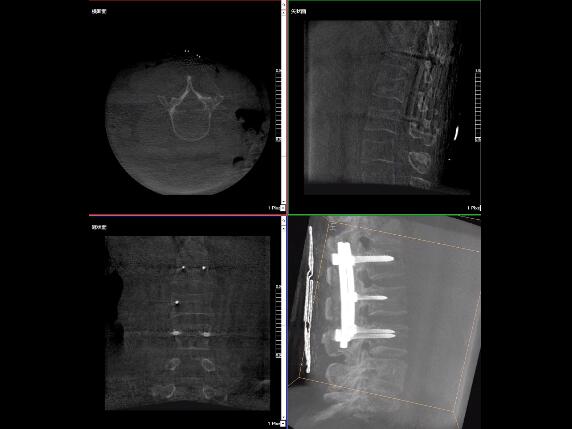

比如,醫(yī)生在做PKP(椎體成形術(shù))的時(shí)候,或者在置入螺釘?shù)臅r(shí)候,醫(yī)生需要在影像上看到螺釘打進(jìn)去的進(jìn)針點(diǎn)以及進(jìn)針的路徑。比如,我們?cè)诖蜓档尼斪訒r(shí)需要看到“貓眼”。我們只有把釘子完全打在“貓眼”里面,才能確保釘子打在了椎弓根里,所以對(duì)“貓眼”的顯影就非常重要。

“貓眼”指的是椎弓根在正位的投影。

最后我要強(qiáng)調(diào)一點(diǎn),以上我提到的“貓眼”,在二維的X光片上,醫(yī)生是靠經(jīng)驗(yàn)去判斷釘子是否打在椎弓根里,這個(gè)時(shí)候如果我們的設(shè)備再先進(jìn)一點(diǎn),診斷手段再多一點(diǎn),如果我們能夠把二維的影像轉(zhuǎn)換為三維的影像,可能就不會(huì)完全依賴(lài)醫(yī)生的經(jīng)驗(yàn)。

我們可以在三維的圖像中直觀的看到釘子到底在不在椎弓根里面,這樣可以指導(dǎo)我們準(zhǔn)確的進(jìn)針,指導(dǎo)我們進(jìn)行一場(chǎng)高質(zhì)量的手術(shù),可以起到事半功倍的效果,手術(shù)會(huì)簡(jiǎn)單得多,病人的預(yù)后也會(huì)好得多。